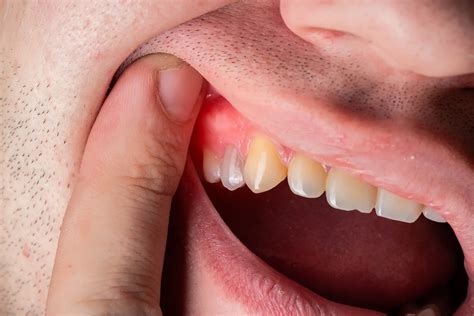

• Visible swelling of the gums, cheek, or jawline.

• Formation of a sinus tract (a small pimple-like bump on the gum that may release pus).

• Severe Dental Decay: Untreated cavities can lead to abscesses that eventually extend into the jaw bone.

• Periodontal Disease: Advanced gum disease causes pockets to form, which can eventually reach the underlying bone structure.